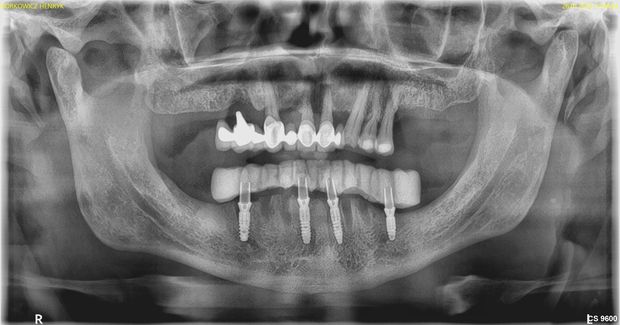

ALL ON FOUR – to odbudowa na czterech implantach całego łuku zębowego. Idealne rozwiązanie dla Pacjentów, którzy nie wyobrażają sobie życia z uzupełnieniem ruchomym.